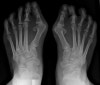

체중부하 상태의 AP view에서 계측합니다.

제1중족골과 무지근위지골의 장축이 이루는 각도가 외반무지각(HV angle)으로 통상 8º 이내, 1530º를 경도, 3040º를 중등도, 그 이상은 중증도입니다.

IM angle이 통상 8º 이내, 13º까지를 경도, 20º까지를 중등도, 그 이상은 중증도입니다.

X-ray : 무지외반증(Hallux valgus)